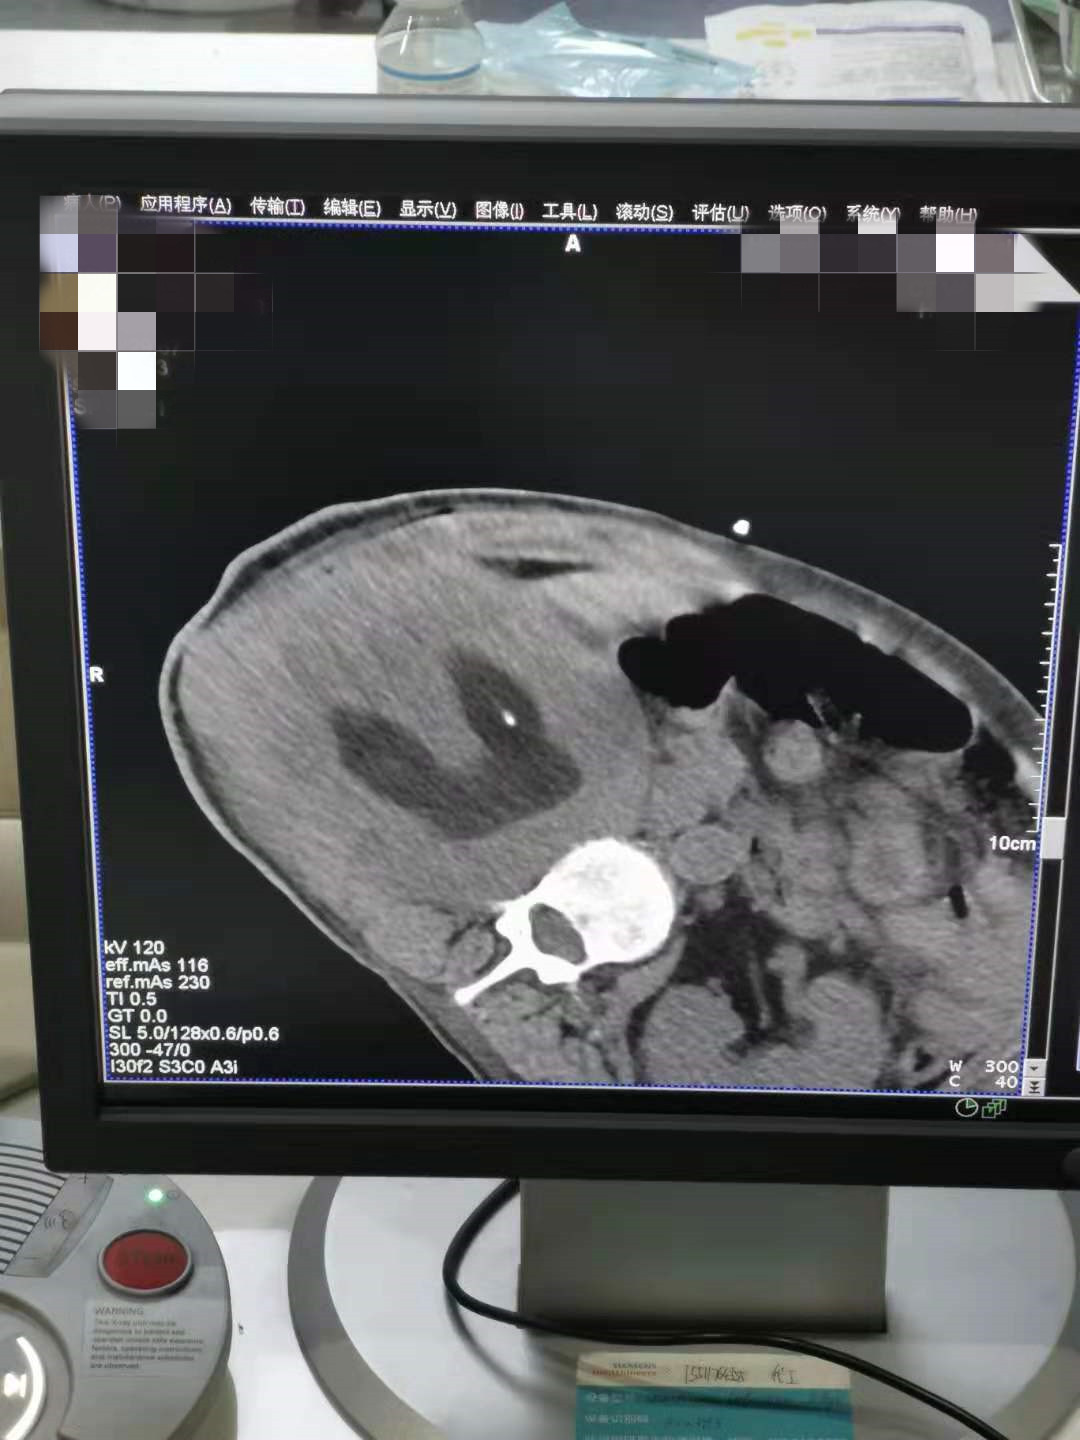

2021年5月份肾部氩氦刀手术